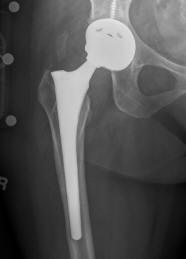

Depuy

Depuy'

Credit: US Drug Watchdog